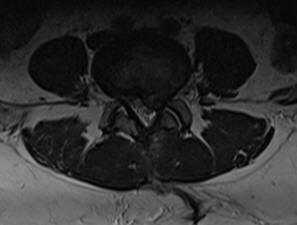

17-MARCH-2025  FATINA ABDEL-QADER KHATAB  50 YEARS  HUGE RECURRENCE L4-5 DISC WITH LEFT FORAMINAL OCCLUSION.

The patient was operated by me 18-November-2024 for extruded disc L4-5 with left upward migration. The patient the last 8 days start  to complain of agonizing LBP with left sciatica down to the heel left foot. MRI lumbar spine done 16-March-2025 showing huge recurrence of the extruded disc L4-5 with left foraminal occlusion. The patient has chronic anemia and Hb now is 10.2 gm/L.

Left L5 foraminotomy was performed. The extruded disc was removed lateral to the axilla and left sided intradiscal cleaning of L4-5 was performed. After removing the huge piece in one fragment, CSF leak took place  fro behind due to scar and adhesion. Using MultiGen, bipolar stimulation of the left L5 root responded to 1.7 Volts. A bipolar pulsed mode RF with 42 Celsius, 240 sec, 2 Hz and 20 msec duration to left L5 root  was achieved using 2 bended catheters 10 mm exposed length. Further bipolar stimulation of the left L5 root responded 1.2 Volts. The root was covered with muscle piece aided with fat. Routine closure of the wound. The left sciatica improved dramatically and she was sent to the ward.

Axial and saggital views of recurrence,